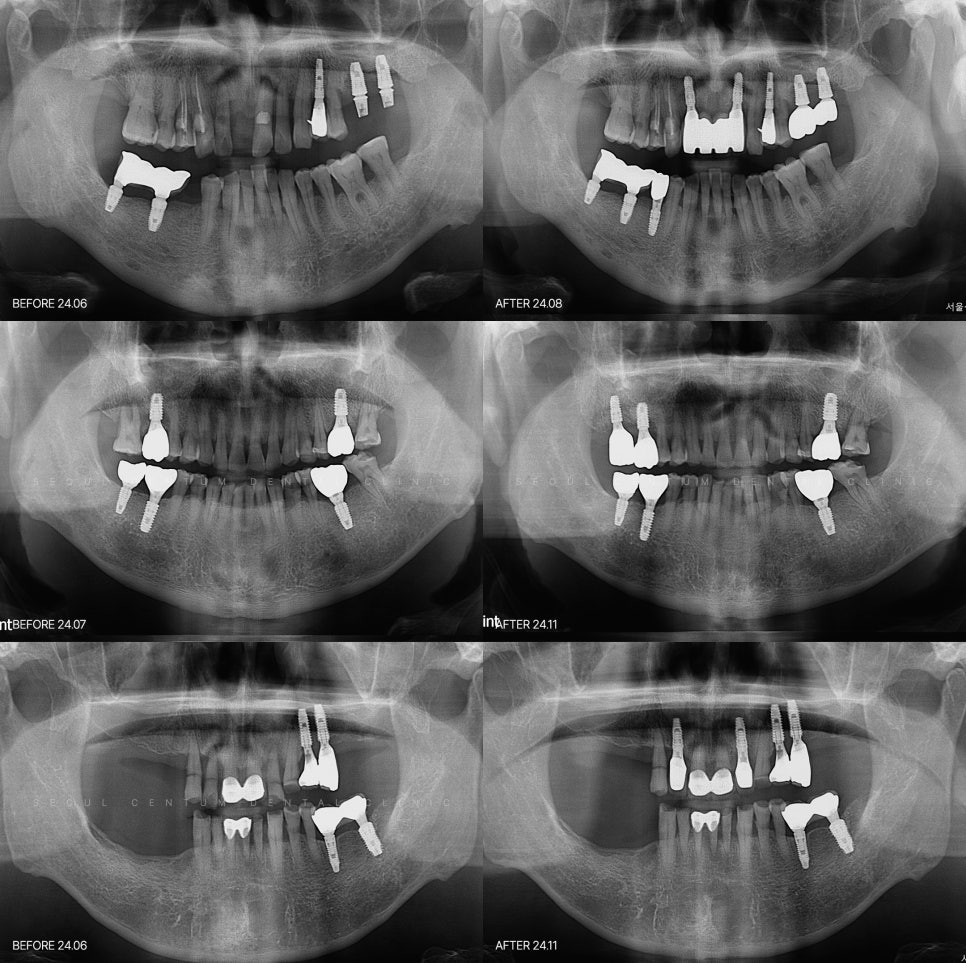

아예 앞니 자체가 상실되어

기능을 하기 어렵게 된 경우에는

전치부 임플란트 보철로 진행되는데

이때는 잇몸의 상태와 뼈상태

치아의 각도 옆의 공간감까지 고려를

해서 진행을 해야합니다.